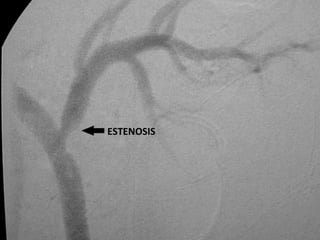

Estrechamiento de una arteria, usualmente ocasionado por obstrucción que puede deberse a acumulación de placa.  El estrechamiento o bloqueo de una arteria coronaria significa que los músculos cardíacos reciben menos sangre y menos oxígeno.

ESTENOSIS